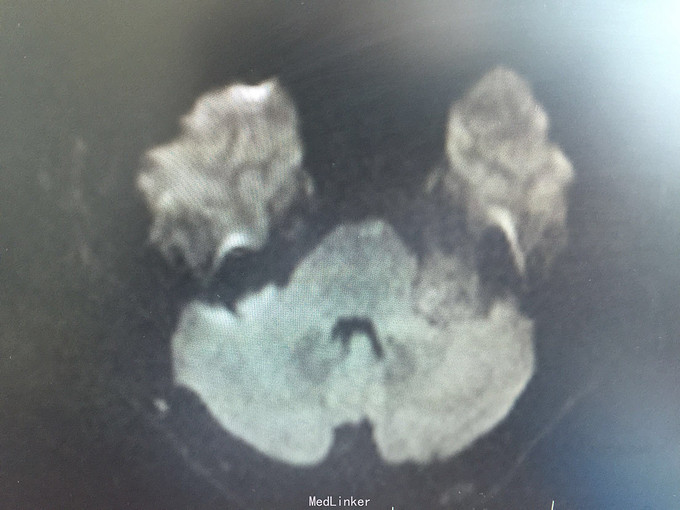

男,52岁,以“左耳鸣、听力下降1年余”入院。 现病史:1年余前看电视时出现左耳鸣、听力下降,左耳听电视声音时听不清,较右侧明显下降,未在意,之后听力下降逐渐至丧失! 既往史:既往高血压、糖尿病病史,长期吸烟病史。 家族史:无特殊!

查体:BP:150/90mmHg,心肺腹未见异常,神清语明,左耳听力丧失,无面瘫,双瞳孔等大正圆,直径约3.0mm,光敏,四肢肌力5级,肌张力正常,巴氏征R-L-。

1.左侧听神经瘤